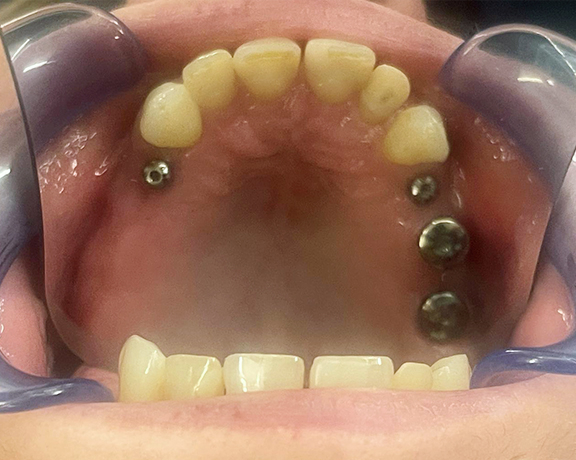

Śruby gojące. Leczenie implantologiczne

Proces leczenia implantologicznego wymaga czasu, zwłaszcza etap osteointegracji, czyli czas zrośnięcia się implantu z kością i jego stabilizacja. Trwa to zazwyczaj kilka miesięcy. W przypadku naszego Pacjenta jesteśmy już krok dalej, tj. po założeniu tzw. śrub gojących. Śrubę gojącą  wkręca się do implantu. Formuje ona brodawkę i kształt przyzębia przy implancie, tak, by były dopasowane do ostatecznej odbudowy protetycznej.

W tym wypadku proces gojenia przebiega znacznie szybciej niż osteointegracja (zazwyczaj 2-3 tygodnie), choć to zawsze kwestia indywidualna. Po tym czasie lekarz usunie u naszego Pacjenta śruby gojące i zamocuje ostateczną odbudowę protetyczną na implantach. Już niebawem pokażemy Wam efekty naszej pracy.